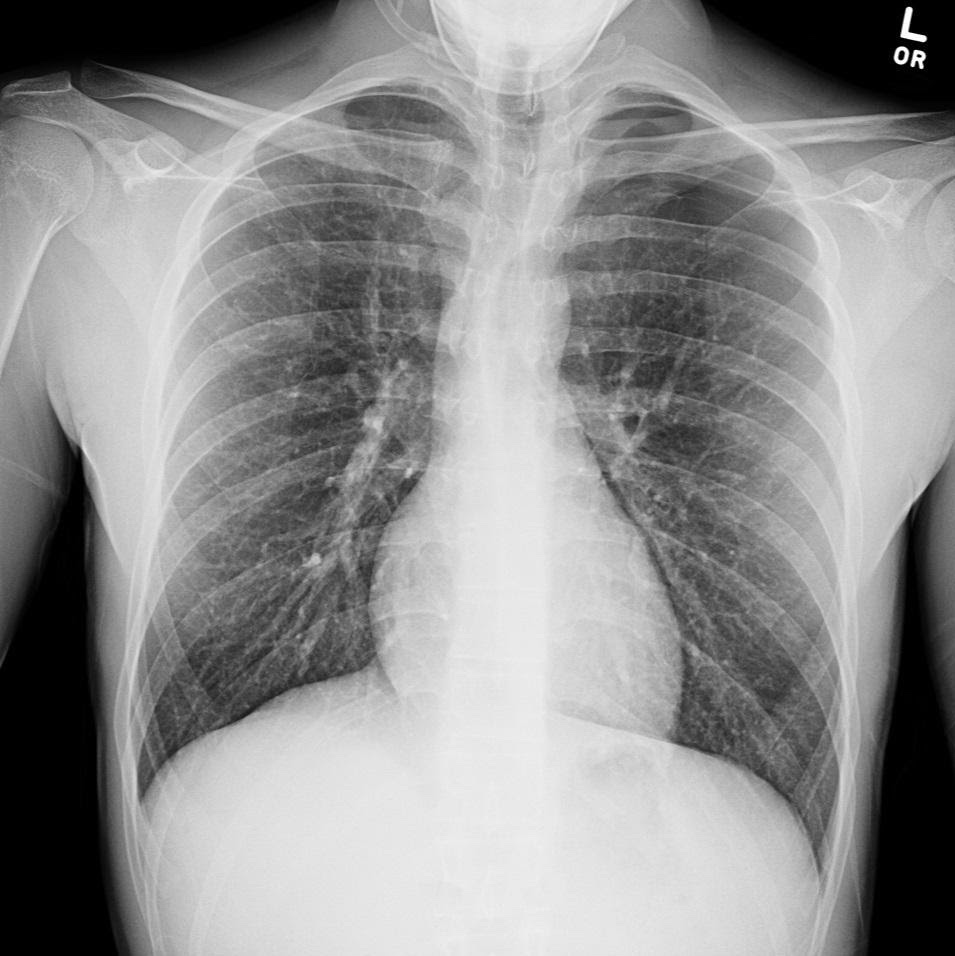

Contributors: Travis Barlock MD, Jeffrey Olson MS4 Feel free to use the cases below for your own practice. All of the scenarios are completely made up and designed to hit several teaching points. Case 1 25 M, presents to the ED with chest pain. Stabbing, started a few hours ago, substernal. Thinks it is GERD. After 2-3 minutes, pain worsens and radiates to the back. VS: BP 125/50 (Right arm 190/110). HR 120. RR of 18. Sat 98% on RA. Additional VS: Temp of 37.2, height of 6'5", BMI of 18. PMH: None, doesn't see a doctor. Meds: None FH: Weird heart thing (Mitral Valve Prolapse), weird lung thing (spontaneous pneumothorax), tall family members with long fingers and toes Physical Exam: Cards: Diastolic decrescendo at the RUSB, diminished S2. UE pulses are asymmetric, LE pulses are asymmetric, carotid pulses are asymmetric, BP is asymmetric MSK: Knees, elbows, and wrists are hypermobile. Imaging: CXR #1 normal, #2 widened mediastinum (no read yet but shows widened mediastinum), POCUS shows small effusion CTA/MRA doesn't come back until after the case. ECG: Sinus Tach Labs: NT-proBNP 500 pg/mL D-Dimer: 7000 ng/L CBC: Hemoglobin: 13.5 g/dL, WBC: 20,000/µL, Platelets: 250,000/µL Chem 7: Na 138, K, 5.7, Cl 102, Bicarb 17, BUN 45, Creatinine: 3.5 mg/dL, Glucose: 180 LFTs: Albumin 2.4, Total protein 5.5, ALP: 140, AST: 3500, ALT: 2800, TBili: 3.2, DirectBili: 2.4, Ca: 7.8 LDH: 2200 PT: 20.5, INR: 2.2, Fibrinogen: 170 5th gen High-Sensitivity Troponin: <3 Lactate: 7 mmol/L VBG: pH 7.22, paCO2 28, bicarb 15 Notes: Can have patient crash somewhere in middle and show 2nd xray Case 2: A 67-year-old female is brought to the ED by her daughter due to progressive weakness, confusion, and fatigue that have worsened over the past week. Unable to get out of bed and has become increasingly lethargic. Also having some nausea, constipation. The daughter denies any preceding illness, recent trauma, or travel. Does not know her meds but will head home to get them after talking with you. VS: BP 88/55 mmHg, HR 110, RR 20, O2 Sat 98% on room air. Additional VS: Temp 36.8°C. PMH: Hypertension, osteoarthritis, and depression. Physical exam: General: Thin, somnolent but arousable. HENT: Dry mucous membranes Neuro: Confused, A&Ox1 (self), hyporeflexia Labs (Includes many that would not return in the ED in case you want to take this case forward to the floor) CBC: WBC 9,500, Hb 16.5, Hct: 50%, Platelets 220,000 Chem7: Na 129, K 2.1, Cl 95, HCO3 34, Creatinine 1.6, BUN 40, Glucose 115 LFTs: normal Magnesium: 1.1 Calcium: 10.8 mg/dL (corrects to 12.8) iCal: 3.2 Phosphate: 2.3 mg/dL Albumin: 2 BUN:Cr ratio: 25 VBG: pH: 7.49, PaCO2 45, HCO3: 34 Lactate: 2.8 Serum Osmolality: 276 mOsm/kg (Osmolal gap of 2) Urine Osmolality: 550 mOsm/kg Urine Sodium (UNa): 10 mEq/L (low). Urine Potassium (UK): 25 mEq/L (elevated). Urine Chloride (UCl): 12 mEq/L (low). Urine Magnesium (UMg): 20 (Elevated). Urine Calcium (UCa): 50 in 24 hrs (Low) 100 cc of urine with foley FeNa Plasma renin activity: 15 mg/mL/hr (elevated), Aldosterone: 25 ng/dL (Elevated), ADH: Elevated, Diuretic screen: Positive for thiazides PTH: 8 (low), HsTrop: 32, Cortisol and ACTH: Normal. EKG: Hypokalemia features CXR: Normal Renal US: shows stones Improves with fluids Note: Can have daughter return with med list at some point including HCTZ, ibuprofen, and sertraline Case 3: Patient Presentation EMS Report: A 27-year-old male involved in a high-speed motorcycle collision is brought to the emergency department by EMS. The patient was found unconscious at the scene with evidence of severe thoracic and extremity trauma. He was intubated en route for airway protection due to altered mental status (GCS 7). VS: HR 130, BP 90/60, RR: bagging at 12 bpm, satting 88% on 100% FiO2 Primary Survey Airway: Endotracheal tube in place. Breathing: Decreased breath sounds on the left side with visible chest asymmetry and paradoxical chest wall movement. Circulation: Mottled extremities noted, with significant deformity of the right thigh. Pulses are diminished in the right leg Disability: GCS remains 7 (E1 V2 M4). Pupils equal and reactive. Exposure: Full-body examination reveals an open fracture of the right femur, multiple abrasions, and bruising over the chest wall. Vent alarms Peak Inspiratory Pressure (PIP) 40 cm H₂O (elevated) Plateau Pressure (Pplat) 35 cm H₂O (elevated) EtCO₂ (End-Tidal CO₂) 55 mmHg High-Pressure Alarm Triggering frequently Glucose 120 CBC: Hgb 8.9, Hct 27, WBC 14.2, platelets 220,000 VBG: pH 7.28, pCO2 33, bicarb 18, lactate 4.5 CXR with tension pneumothorax Patient improves after chest tube, pigtail catheter, or needle decompression. Ready to be transferred upstairs and O2 starts tanking again Vent alarms- second episode Peak Inspiratory Pressure (PIP) 35 cm H₂O (elevated) Plateau Pressure (Pplat) 30 cm H₂O (elevated) EtCO₂ (End-Tidal CO₂) 20 mmHg HR: 140, satting 84%, temp 38.5, ABG: pH 7.32, pCO₂ 30 mmHg, pO₂ 60 mmHg on 100% FiO₂, HCO₃⁻ 18 mmol/L (hypoxemia and metabolic acidosis). D-dimer: Elevated Thrombocytopenia: Platelets 90,000/µL. US shows blown right ventricle ECG shows new RBBB CT PE: Ground glass opacities, consolidation, centrilobular nodules, septal thickening, and fat-attenuating lesions. Note: Management is largely supportive care so once the diagnosis is made, end the case. References Carroll MF, Schade DS. A practical approach to hypercalcemia. Am Fam Physician. 2003 May 1;67(9):1959-66. PMID: 12751658. Coelho SG, Almeida AG. Marfan syndrome revisited: From genetics to the clinic. Rev Port Cardiol (Engl Ed). 2020 Apr;39(4):215-226. English, Portuguese. doi: 10.1016/j.repc.2019.09.008. Epub 2020 May 18. PMID: 32439107. Palmer BF. Metabolic complications associated with use of diuretics. Semin Nephrol. 2011 Nov;31(6):542-52. doi: 10.1016/j.semnephrol.2011.09.009. PMID: 22099511. Reed MJ. Diagnosis and management of acute aortic dissection in the emergency department. Br J Hosp Med (Lond). 2024 Apr 30;85(4):1-9. doi: 10.12968/hmed.2023.0366. PMID: 38708978. Roberts DJ, Leigh-Smith S, Faris PD, Blackmore C, Ball CG, Robertson HL, Dixon E, James MT, Kirkpatrick AW, Kortbeek JB, Stelfox HT. Clinical Presentation of Patients With Tension Pneumothorax: A Systematic Review. Ann Surg. 2015 Jun;261(6):1068-78. doi: 10.1097/SLA.0000000000001073. PMID: 25563887. Rothberg DL, Makarewich CA. Fat Embolism and Fat Embolism Syndrome. J Am Acad Orthop Surg. 2019 Apr 15;27(8):e346-e355. doi: 10.5435/JAAOS-D-17-00571. PMID: 30958807. Produced by Jeffrey Olson, MS4 Special thanks to Evan Fisch MD Get your tickets to Tox Talks Event, Sept 11, 2025: https://emergencymedicalminute.org/events-2/ Donate: https://emergencymedicalminute.org/donate/